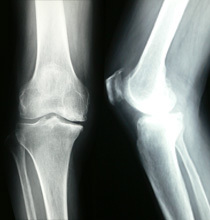

人工関節置換術とは?

人工関節手術は、変形性関節症や関節リウマチ、あるいは外傷によって傷んで変形した関節の表面を取り除き、人工の関節に置き換えて関節の痛みを軽減する手術です。肩、肘、手指、股、膝、足と様々な関節に対して行われます。高齢の患者が手術の対象となることが多く、人工関節手術件数はどの関節分野においても年々増加しています。

人工膝関節症とは?

人工膝関節症については、専用のページをご確認下さい。